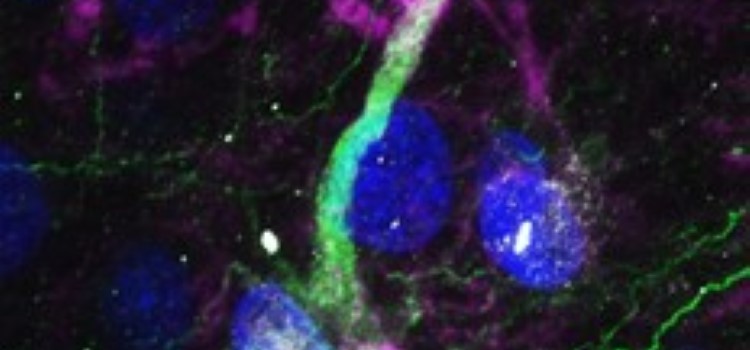

Demuestran la existencia de células madre en el cerebro humano 25.10.2021 Las enfermedades neurodegenerativas atacarían a las células madre del cerebro impidiendo la generación de nuevas neuronas